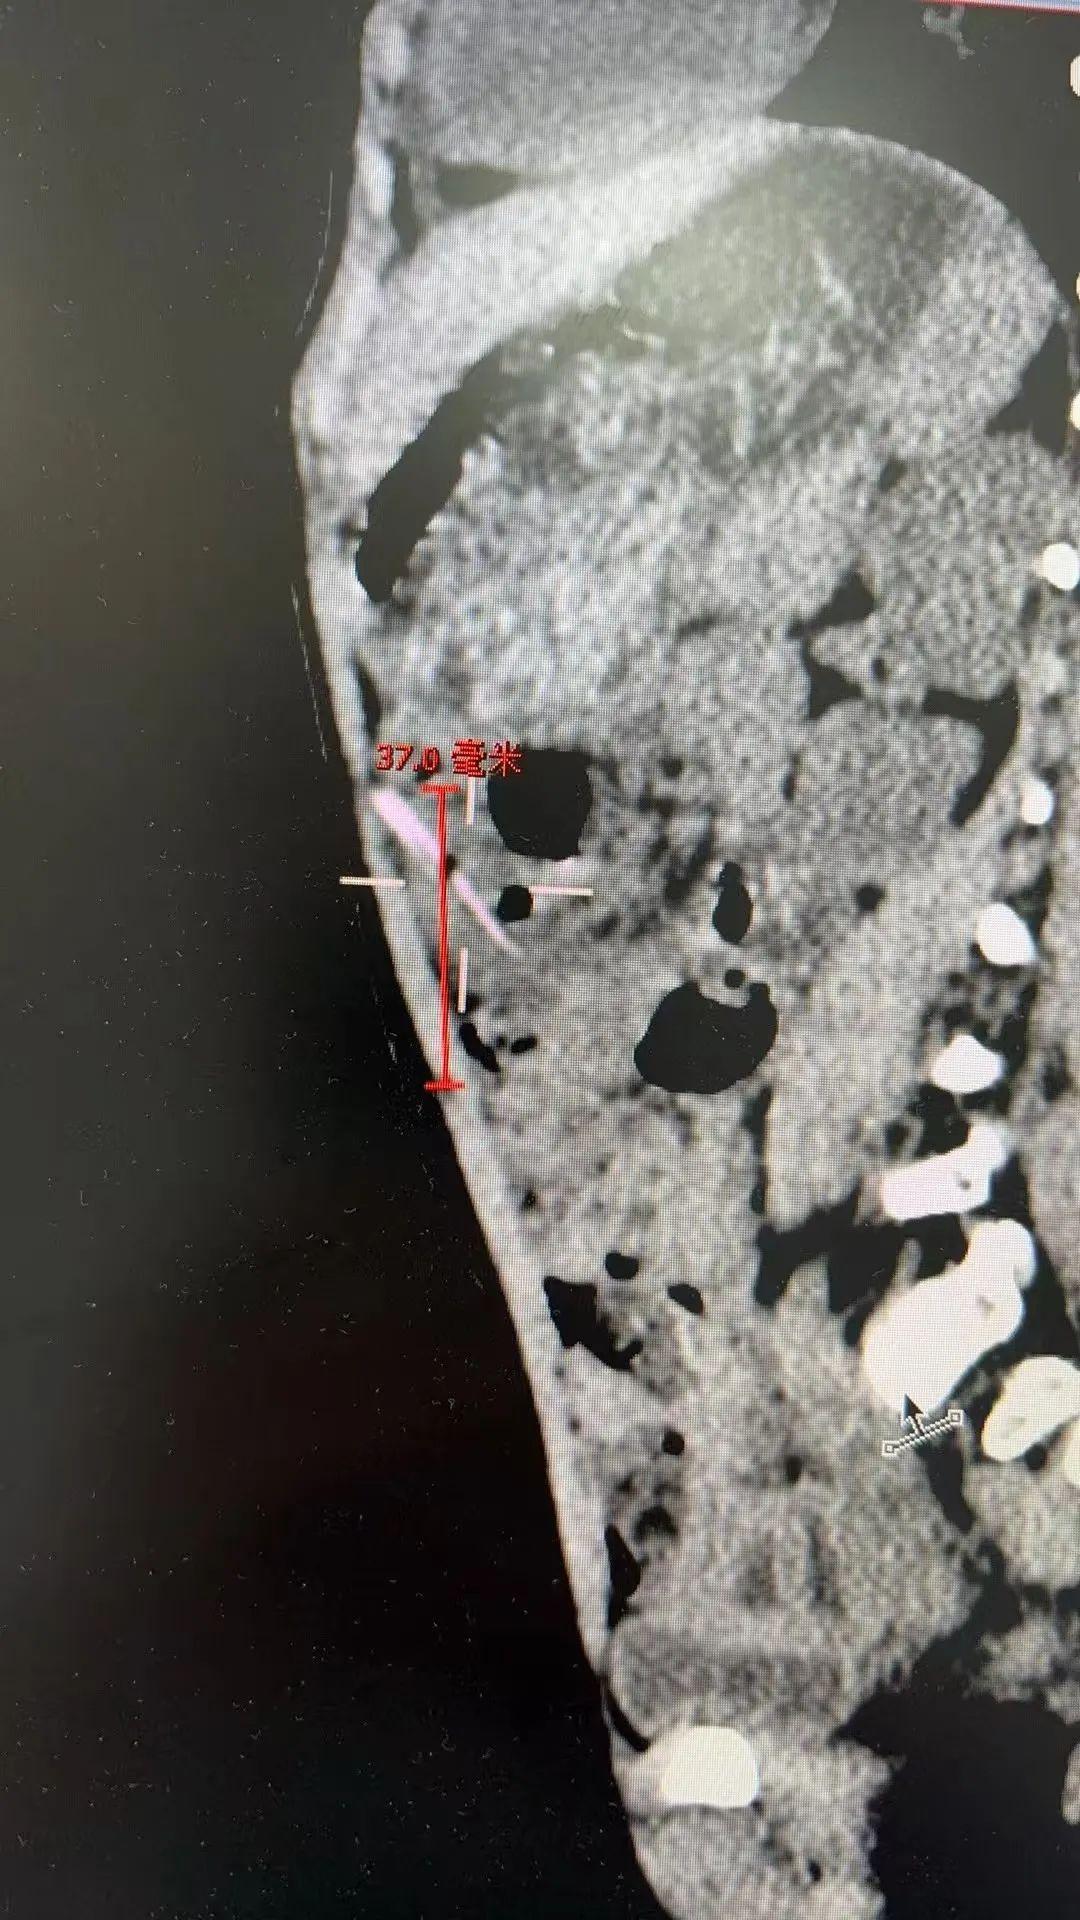

兒童普通外科副主任張伊凡聽添添父母講述了病史,查看孩子並無感冒症狀,推測腹痛很有可能與誤食異物有關,隨後的腹部CT檢查發現孩子腹腔內疑似存在約2.5釐米長的異物,張伊凡立即建議孩子住院治療。

入院後,添添的症狀有所好轉,父母抱着或許能自己排出的期待,希望暫緩手術繼續觀察,可是兩天後複查CT,異物還在寶寶的肚子裏紋絲未動。

爲了避免延誤治療,在徵得家長同意後,爲添添實施腹腔鏡微創手術。術中探查結果令人心驚:一根長約2~3釐米的尖銳竹籤,已穿透患兒腸管,深深刺入腹腔!萬幸的是,竹籤未傷及其他重要臟器,也未引發嚴重感染。